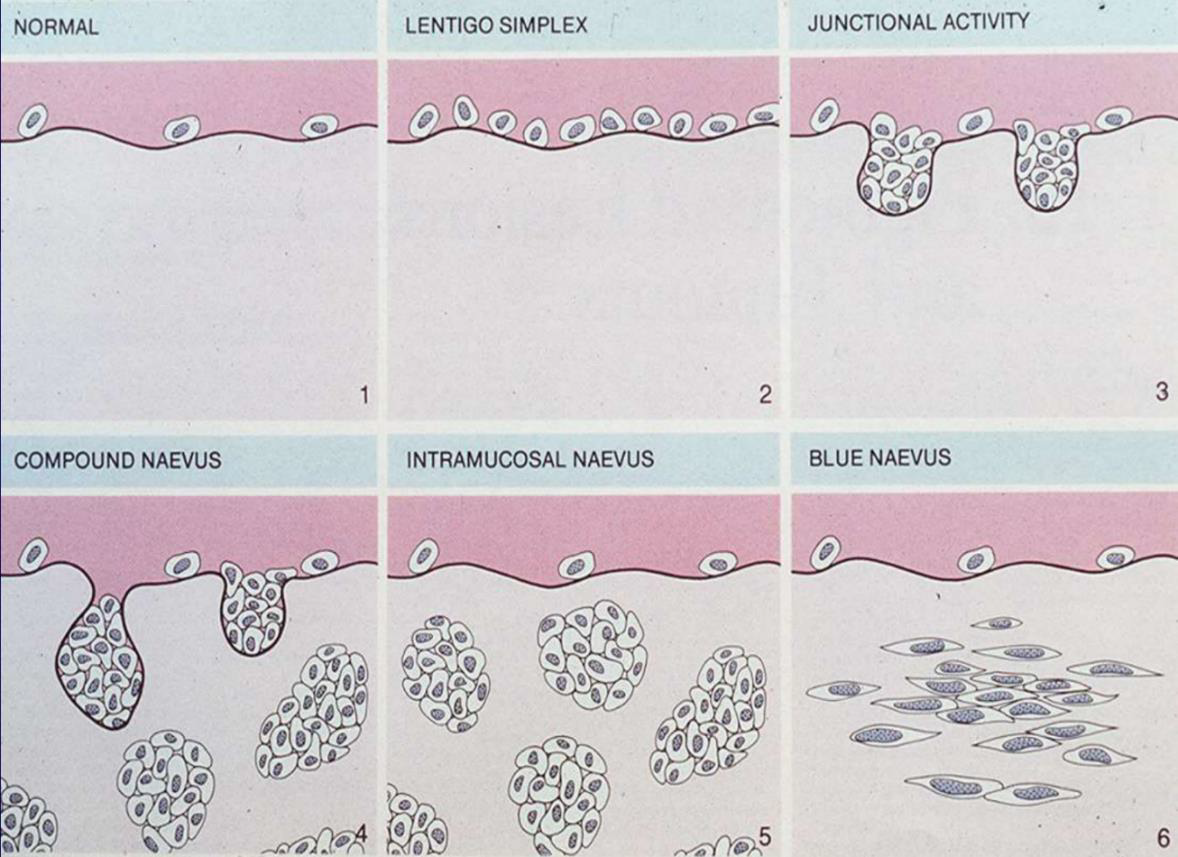

Naevus

- Naevus cell 無 Dendrites

- 位置:

- 先天: 四肢,口內少見

- 後天: NRAS(大 lesion,6%), BRAF(小 lesion,80%) mutation (3.~5.是一個漸進的過程)

- 先天: 四肢,口內少見

Intraoral melanocytic Nevus

- 後天,口內,最常見

- 位置: Palate,mucobuccal fold, orgingiva

- BRAF

- 35y

Blue nevus

- 後天,口內,次常見

- 位置: Palate

- GNAQ mutation

組織

- Cell 分三類:

- A: Epithelioid (在 epi)

- B: Lymphocyte-like

- Spindle-shaped

- Compound (在 epi., dermis 之間) 或 Intradermal

- 只有 Junctional 會呈現 Tear-like Nest

- Indian-file pattern: 鑽進 Dermis 排成一排

- 深層可能圍皮膚附屬物、神經